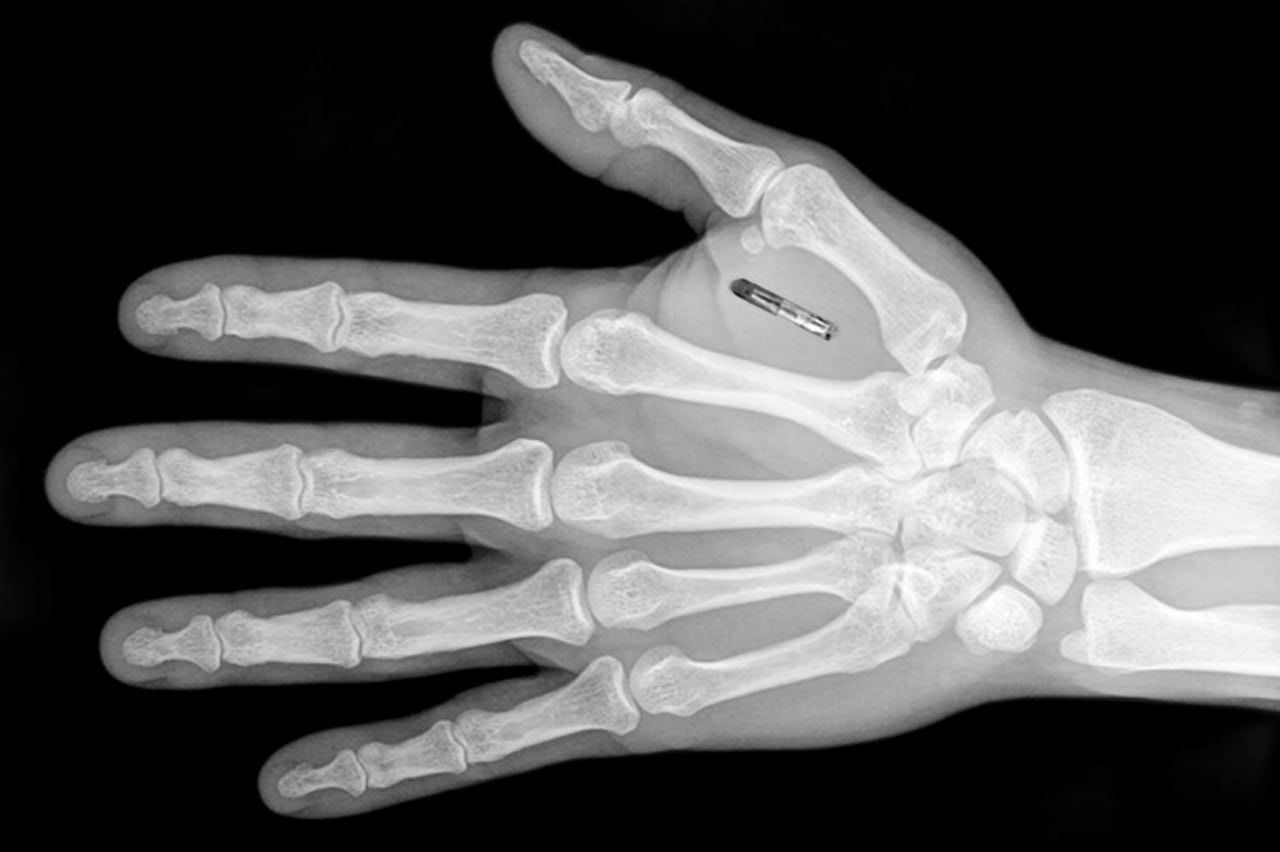

Implanting Chips into Employees

No more identifications badges a Swedish office block is taking security to the next level. The hi-tech building implanted a microchip ...